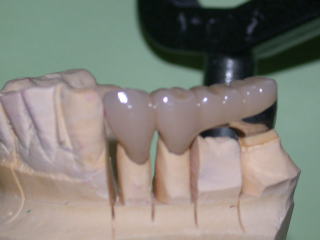

平成20年3月、上部構造物4本を装着しました。

咬合面観です。

構造は白金加金製の金属フレームに、セラミックスを焼き付けてあります。

金属だけよりも審美性に優れ、セラミックスだけよりも耐久性は向上しますが、製作手順が複雑です。

歯科技工士の熟練した技術が必要となり、金額も高めです。

歯肉の状態は前回型取り時より平坦化して、炎症も治まりつつあります。

口腔内に試適し、色や形なども患者さんに確認してもらいます。